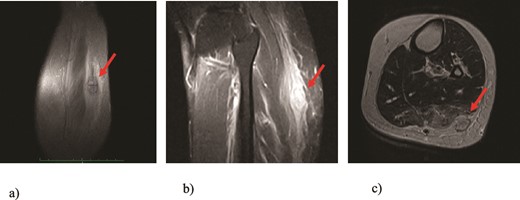

We present a case of a 49-year-old, female patient who presented at our clinic complaining of a growing painful mass with a diameter of ⁓3 cm in her left calf. The patient noticed the mass 2 months before the clinical exam and according to the anamnestic data it was growing progressively, becoming more painful, but only when touched, not spontaneously. She was first seen in another clinic, an ultrasound was performed and excision in local anesthesia was suggested. On presentation, clinical and ultrasound examinations were performed. Clinical exam revealed presence of a soft tissue mass on the medial side between the proximal and medial third of the left calf, of ⁓3 cm. It was placed deep in the subdermal area, mobile and not connected to the fascia. The ultrasound showed a heterogeneous, but predominantly hypoechoic mass with increased through transmission and increased vascularization (Fig. 1). Magnetic resonance imaging (MRI) was performed, confirming the presence of a soft tissue tumor in the subcutaneous tissue of the left calf (Fig. 2). Wide resection of the mass under spinal anesthesia was scheduled. Macroscopy of the specimen showed a whiteish soft fragment measuring 2 × 2 × 0.8 cm, microscopically composed of fibroblastic stroma with myxoid degeneration and immature osteoid embedded in between atypical osteoblasts with inconspicuous mitotic activity (Fig. 3). Foci of chondroid matrix with atypical chondrocytes were present. Necrotic and calcified bony trabeculae with osteoblastic rimming and adipose tissue with skeletal muscle were present on the periphery. The proliferative index, Ki67 was ⁓5%, thereupon a diagnosis of low-grade ESOS was made (Fig. 4). The regular staging follow-up was performed with chest and abdominal computed tomography (CT). No signs of metastatic disease were detected. The bone scan with Tc99m showed an increased uptake on the left iliac bone, highly suspected of Paget disease. Another surgery was scheduled. This time, re-resection procedure to achieve negative margins, as well as a biopsy of the iliac wing was performed. Negative margins were accomplished with the re-resection procedure. Grossly, the iliac bone biopsy was composed of five bony fragments measuring 0.5–1.5 cm. Microscopy showed sclerotic and irregularly shaped anastomosing, lamellar bony trabeculae with focal irregular calcification. The trabeculae contain osteocytes without atypia, rimmed with reactive osteoblasts, as well as multinucleated osteoclast giant cells. Granulation tissue with focal collagen deposition was present focally in between the bone trabeculae. Focal bone marrow was present. The microscopic analysis was consistent with the late (sclerotic) phase of Paget disease of bone (Fig. 5). On the last follow-up exam, 2 years after the surgery there is no evidence of local recurrence.

Microscopic appearance, from the biopsy of the iliac wing, showing late (sclerotic) phase of Paget disease, He-Eo, ×200.